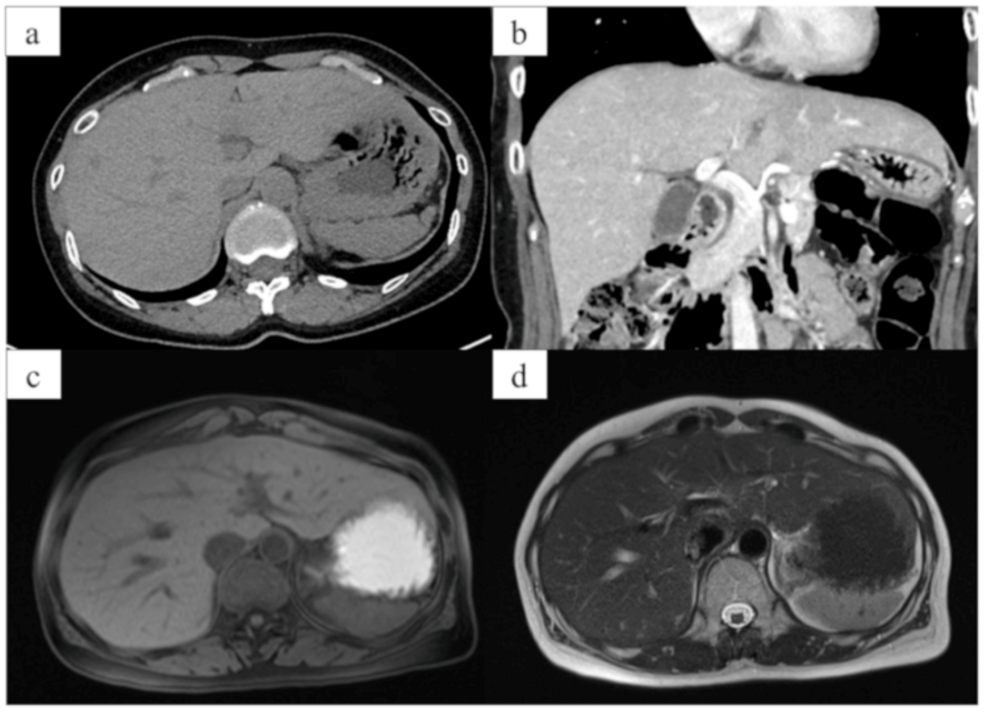

Article river e4daaa909e0b11f0b6ef6784e055ea17 figure.1